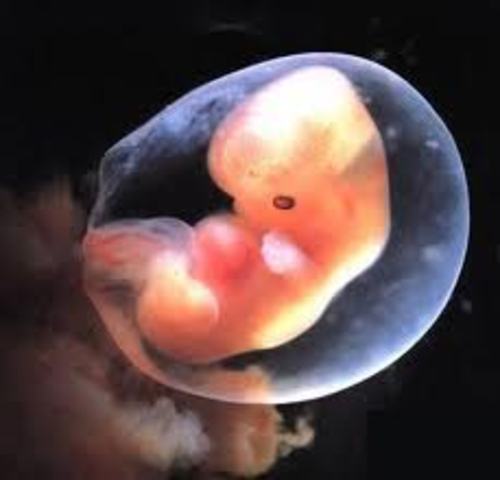

• week 5

week 5

The amniotic fluid is being built up.

The embryo grows from a tiny speck about 2mm - the size of a pin head.

By the end of the week the embryo will have more than doubled in size to about 4-5mm.

The egg has now completely grown into the mucous membrane of the uterus which covers the egg, the umbilical sac and the amniotic fluid cavity.

A fibrin clot closes the hole to the uterus cavity.

The placenta is developing.

The embryo starts receiving oxygen and nutrition through the placenta.